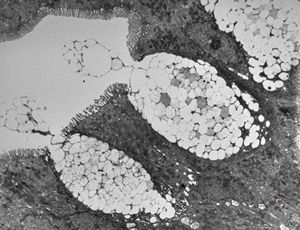

M,35y. | duodenum … lipid malabsorption - susp. hypo-beta-lipoproteinemia